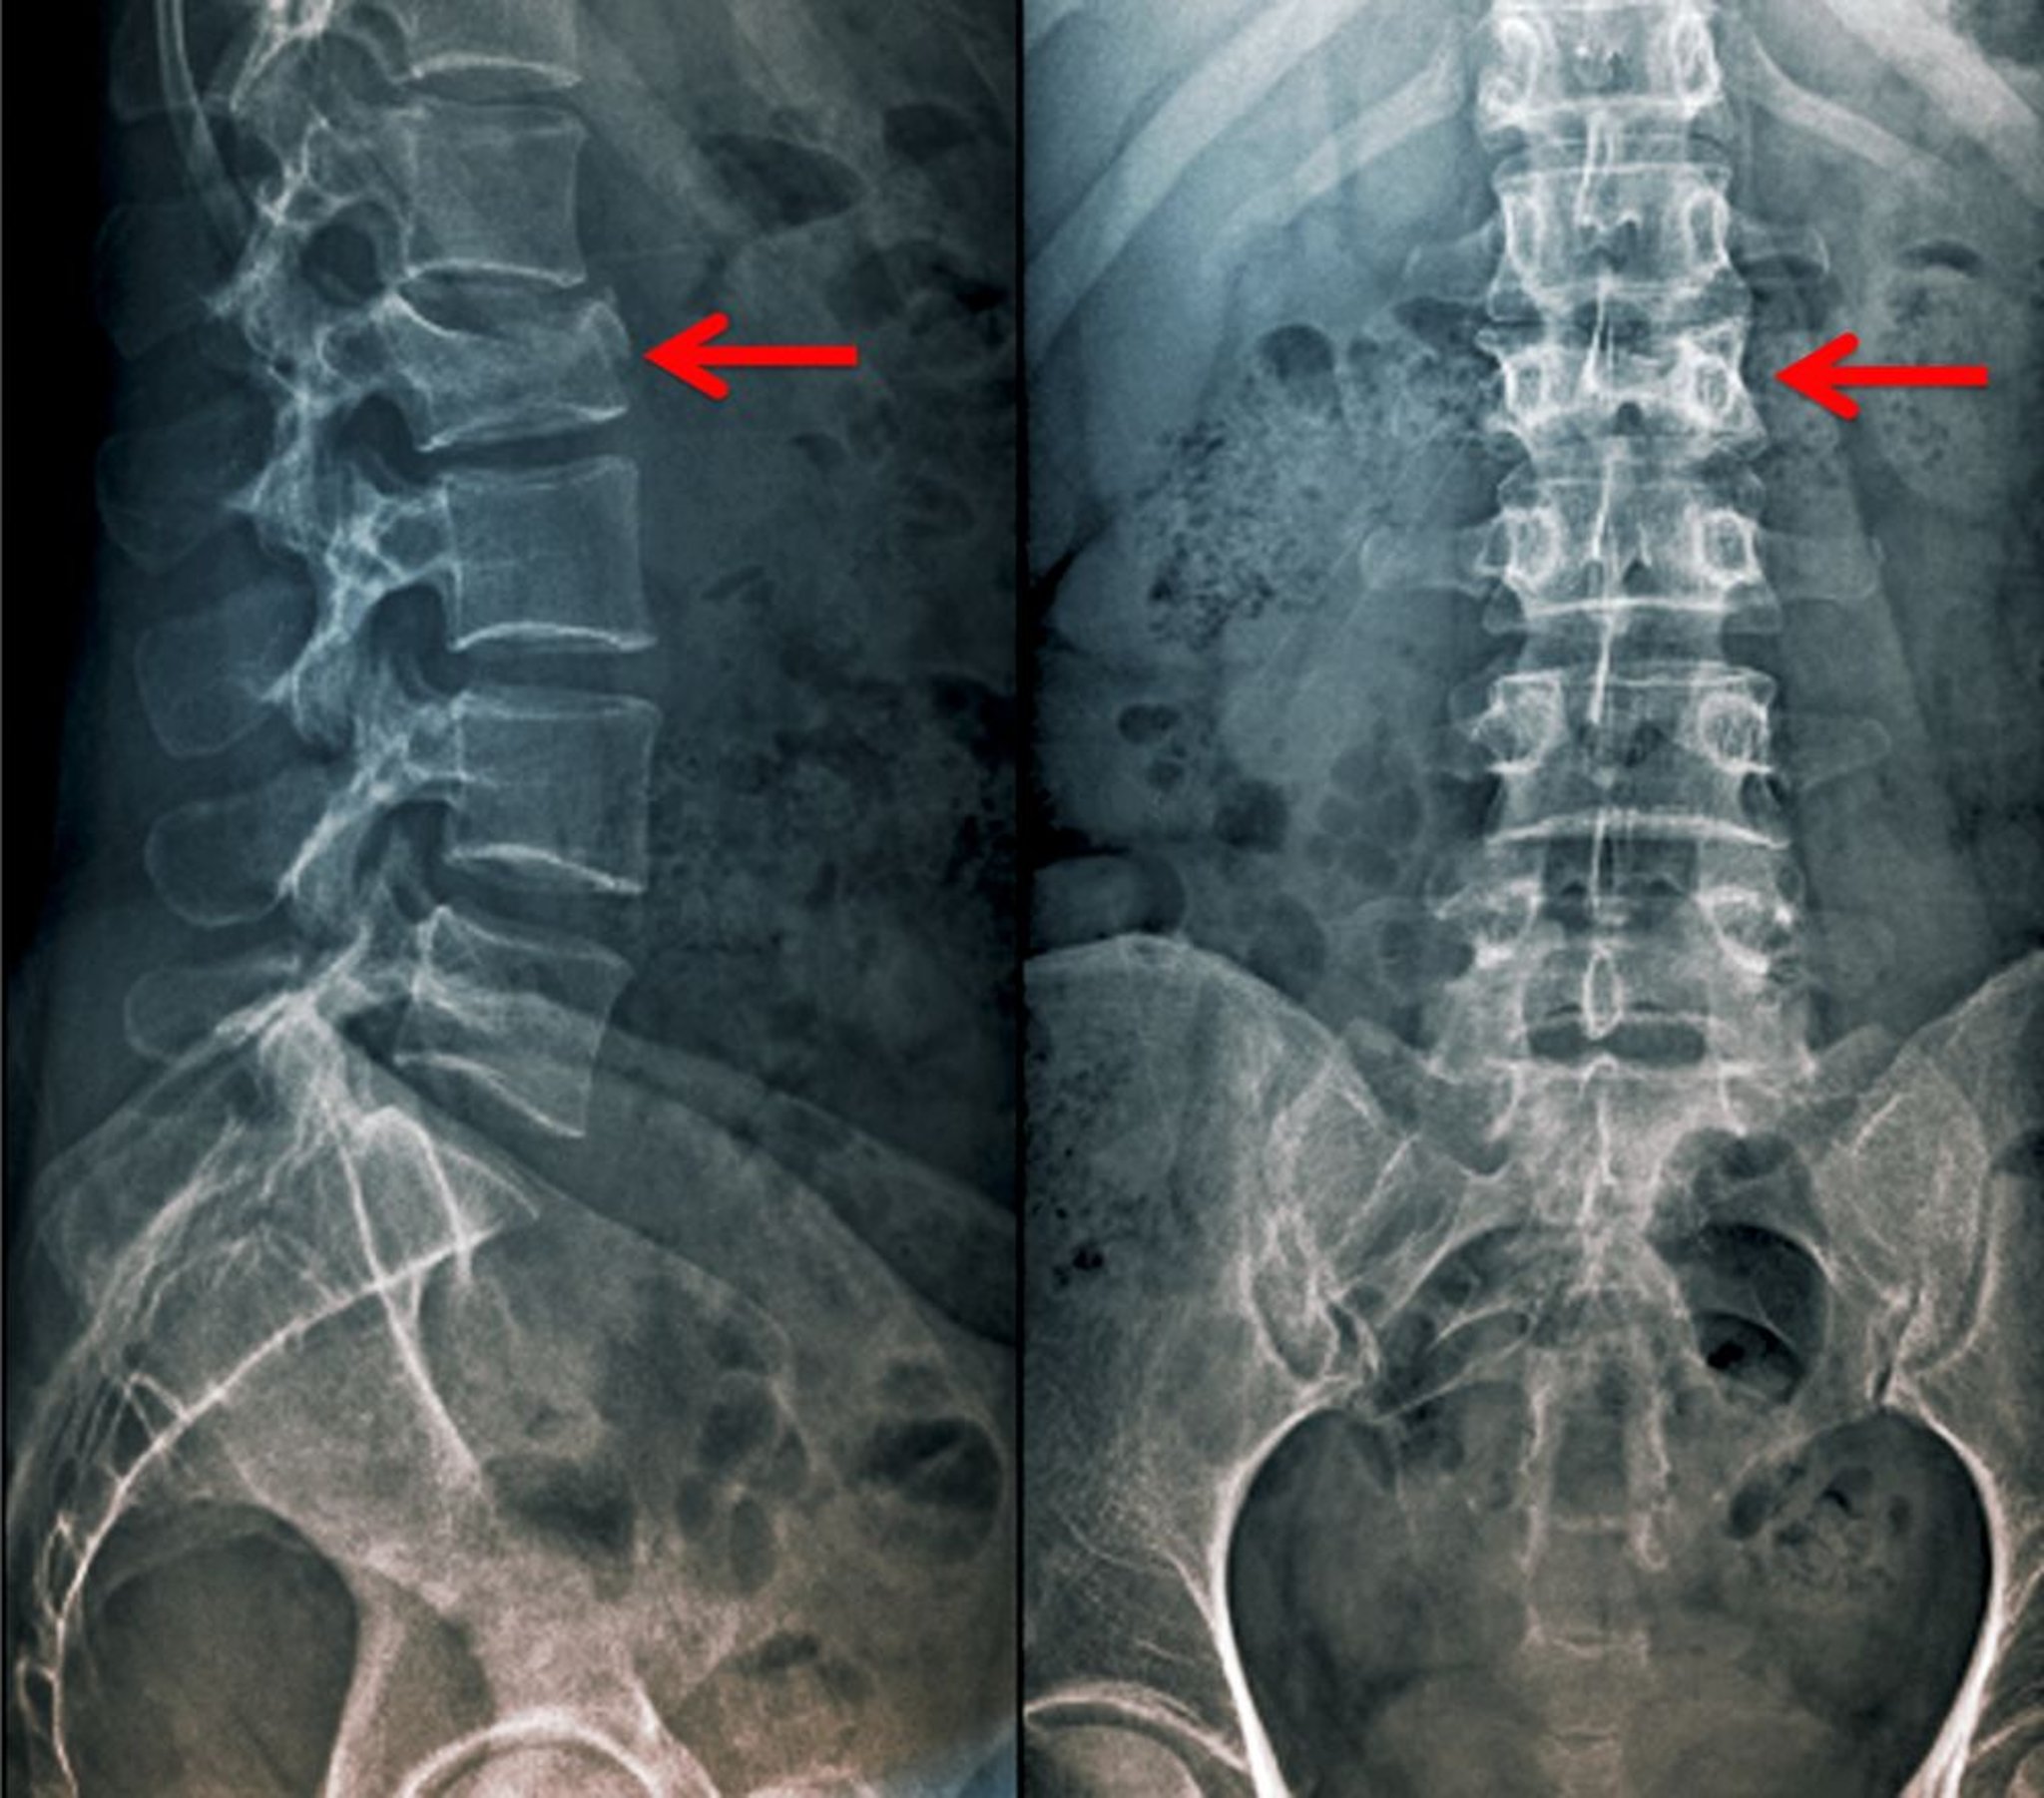

Incidenza anteroposteriore e laterale di una frattura da compressione

Questa frattura da compressione della 2a vertebra lombare è visibile come una perdita di altezza del corpo vertebrale sia nella proiezione antero-posteriore che laterale.